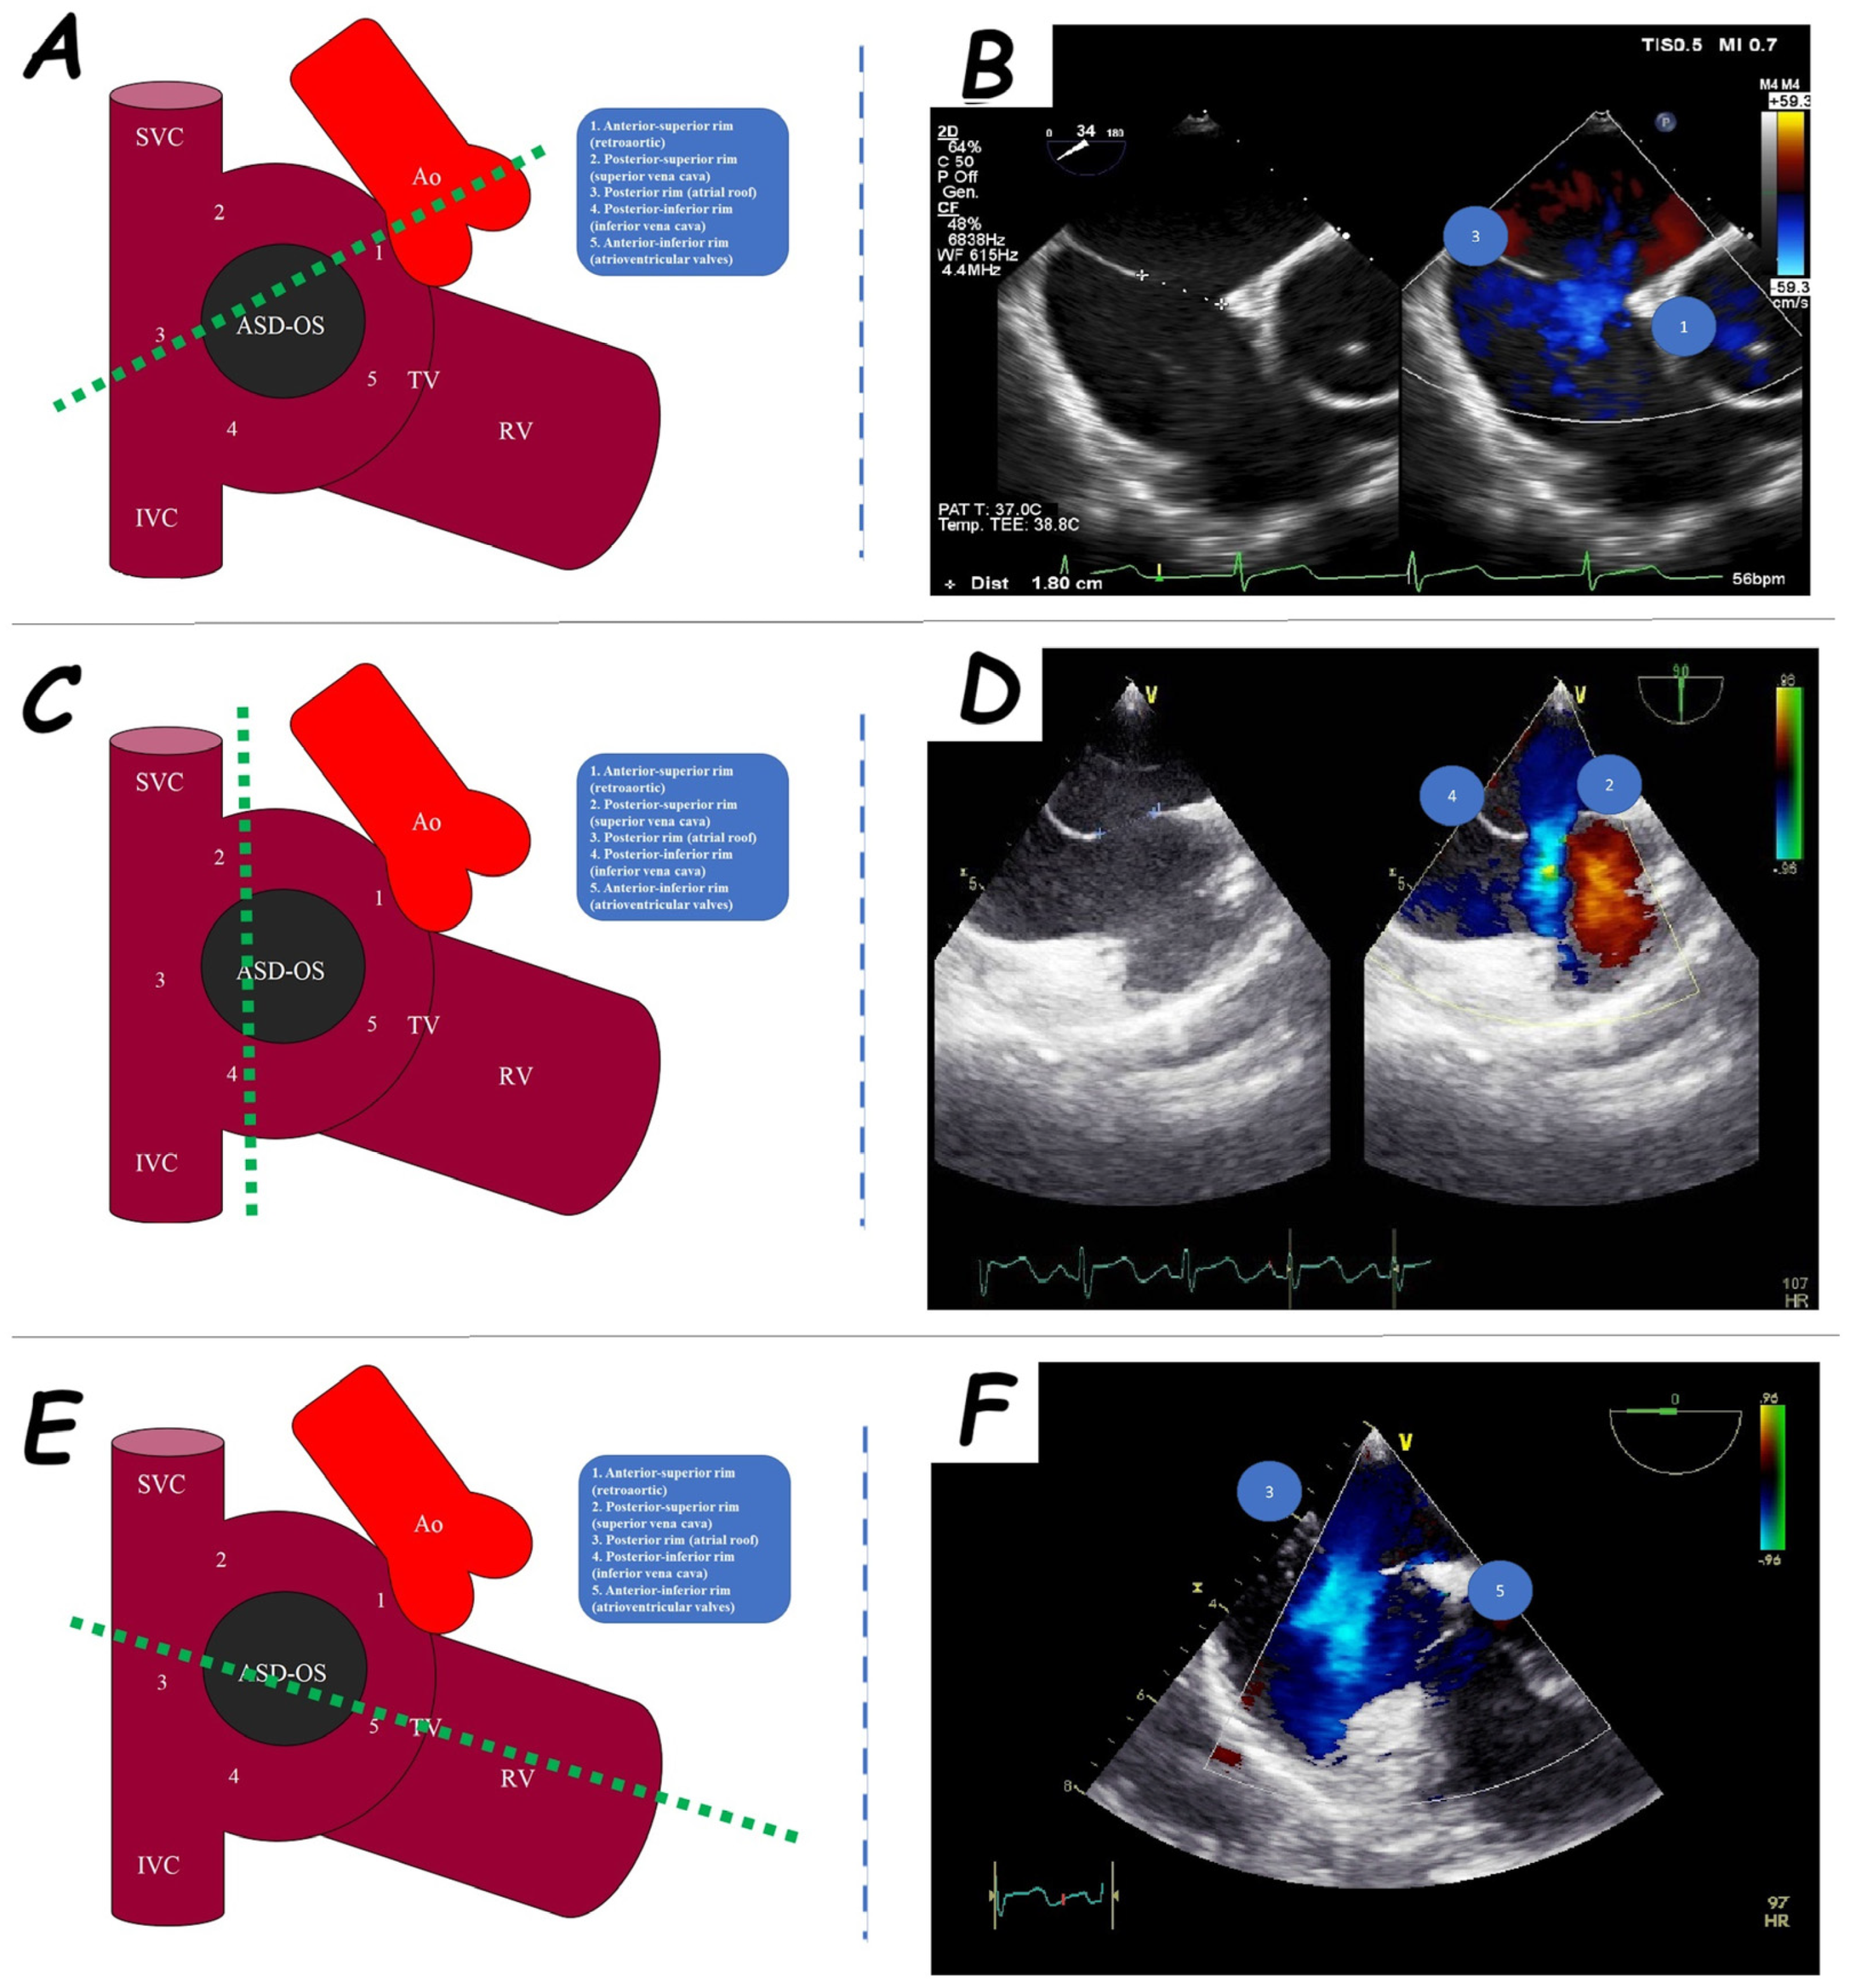

2. Atrial Septal Defect Closure

| ASD Closure: Pre-Procedural Assessment | |

|---|---|

| ASD shape | elliptical, round or irregular shapes (star-, reniform- or other irregular shapes), internal seedings |

| ASD size | maximum ASD diameter |

| ASD shunt direction | left-to-right, bidirectional, or right-to-left |

| ASD periorificial rims | adequate (>5 mm), poor (<5 mm), or absent |

| Accessory ASDs | numbers, size, and distance (if present) |

| Atrial septum aneurysm | base width and an aneurysm excursion into the right or left atrium (if present) |

| Misaligned ASD | distance of separation between the septum primum surface and the septum secundum one (if present) |

| Double atrial septum | separation between the left atrial and right atrial rims of the defects (if present) |

| Redundant Eustachian valve | length and excursion (if present) |

| Chiari network | width and extension (if present) |